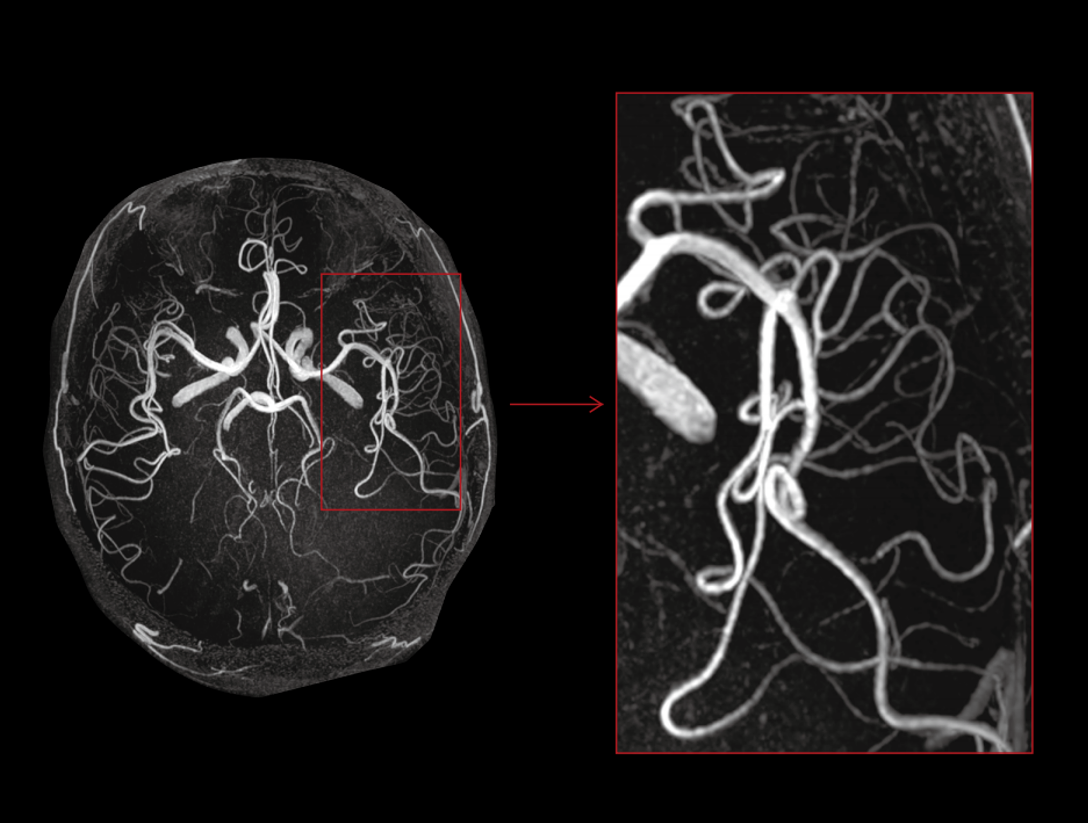

32/48 고밀도 RF 채널은 통합 고밀도 코일과 함께 사용되어 이미지의 신호 대 잡음 비율(SNR)을 크게 향상시킵니다.